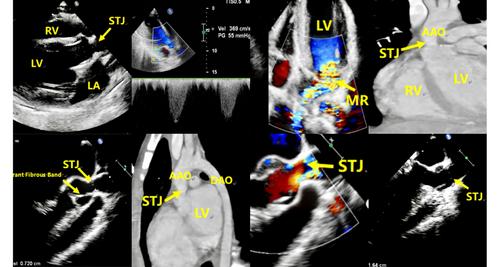

经食管超声心动图(TEE)显示,瓣上主动脉狭窄是由连接左冠状动脉尖端和窦壁的异常纤维带引起的。本病例强调TEE在描绘此类异常解剖和指导精确病因诊断和手术计划方面的优势。

Transesophageal echocardiography (TEE) revealed that supravalvular aortic stenosis was caused by an aberrant fibrous band bridging the left coronary cusp and the sinus wall. This case highlights the advantage of TEE in delineating such abnormal anatomy and guiding precise etiological diagnosis and surgical planning.